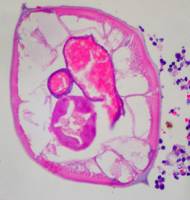

Giun kim đôi khi được chẩn đoán tình cờ qua giải phẩu bệnh. Hình ảnh giun kim qua nhuộm hematoxyline và eosin. |   !important;Hình ảnh phóng đại của giun kim trong tiêu bản cắt ngang, nhuộm hematoxyline và eosin |   !important;Hình ảnh giun kim đực trong lát cắt ngang, alae (mũi tên xanh), ruột (mũi tên đỏ) và tinh hoàn (mũi tên đen) |

Hình 11. Giun kim trong lòng ruột thừa và giải phẩu bệnh dưới kính hiển vi.